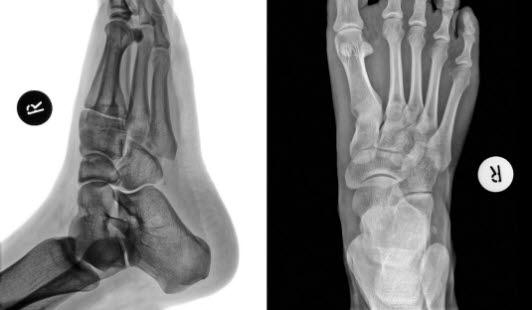

Köhlers sykdom er en smertetilstand i mellomfoten eller forfoten. Sykdommen skyldes at ett av de små beina i foten får nedsatt blodforsyning, og deler av beinet henfaller, synker sammen (aseptisk nekrose). Tilstanden er vanligvis ensidig. Det skilles mellom Köhler I og II. Ved Köhler I er det båtbeinet (os naviculare) som er skadet, mens ved Köhler II er det et av de lengre fotbeina (metatars 2 eller 3) som er skadet (se røntgenbilde over av normal fot). Köhler II betegnes også Freibergs sykdom.

Ved undersøkelse angir barnet smerter, ømhet og det kan være hevelse i mellomfoten (Köhler I) eller i forfoten (Köhler II). Røntgen kan vise typiske forandringer.